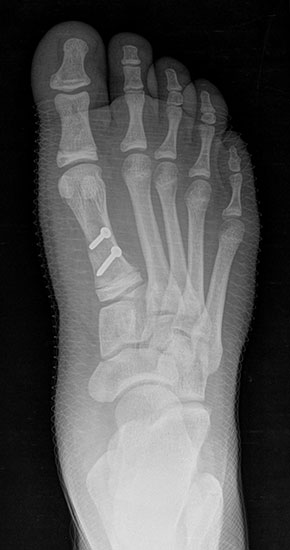

Röntgen

Standard ist die belastete Röntgenaufnahme des Fußes dorso-plantar und seitlich. Günstig ist eine Röhrenkippung von 10°-20°, um die Gelenke der Lisfranc-Linie einsehen zu können.

Ergänzend kann eine Schrägaufnahme hilfreich sein. Bei Metatarsalgien oder Pathologien der Sesambeine liefert die Sprinteraufnahme zusätzliche Informationen. Bei einer Pes planovalgus Fehlstellung wird ergänzend ein Saltzman view durchgeführt.

• Hallux valgus Winkel

• Hallux valgus interphalangeus Winkel

• Intermetatarsalwinkel I zu II

• Distaler Metatarsale Gelenkwinkel (PASA)

• Form des Mittelfußknochenkopfes

• Winkel Metatarsale I Basis zum Os cuneiforme mediale

• Metatarsalindex

• Elevation/ Plantarisierung I. Strahl

• Pes metatarsus adductus

• Wachstumsfugen

• Coalitiones

• Akzessorische Knochen